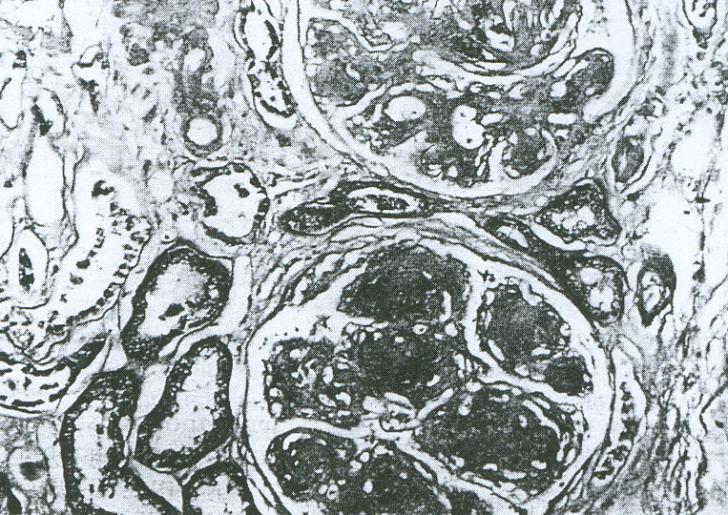

Nefropatia diabetica (ND) Nefropatia diabetica (ND) este o complicatie cronica a diabetului zaharat (DZ), ce apare atat in DZ tip 1 cat si in DZ tip 2, la 20-40% din cazuri si reprezinta cea mai frecventa cauza a bolii cronice deCiteste tot ... 19089 cuvinte

Dimensiune mare + cu imagini |